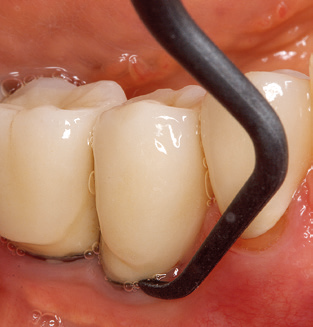

L'aggiornamento della storia medica del paziente è un aspetto importante di SPT e dovrebbe avvenire almeno una volta all'anno. Aiuta il team dentale a identificare e documentare eventuali nuovi fattori di rischio. Soprattutto quando un paziente viene curato per molti anni, è importante stabilire se i fattori di rischio per la salute specifici del paziente e generali sono cambiati. Ciò riguarda principalmente un aumento del rischio a causa del diabete, ma altre condizioni generali (malattie cardiovascolari e neoplasia) possono anche produrre un profilo di rischio modificato a seguito del trattamento eseguito e della somministrazione dei farmaci. Di conseguenza, l'aggiornamento della storia medica come parte di SPT è molto importante, poiché un profilo di rischio modificato può innescare la necessità di adattare l'intervallo di trattamento. Nel passaggio successivo, è importante prestare la dovuta attenzione alla diagnostica. Mentre gli strumenti sono un aspetto centrale di SPT, i risultati e la loro documentazione non devono mai essere trascurati. I risultati parodontologici sono essenziali per una buona diagnosi; aumenti della profondità della tasca e l'indice BOP sono chiari indicatori dell'avanzamento della malattia parodontale e perimplantare. Pertanto, il team non dovrebbe evitare di sondare anche gli impianti, con l'obiettivo di raccogliere i dati richiesti. Allo stesso tempo, è importante utilizzare sonde parodontali con segni millimetrici. Le sonde metalliche sono già state utilizzate per determinare la profondità della tasca attorno ai denti naturali per decenni. Nel caso degli impianti, la sfida di registrare profondità delle tasche corrette e riproducibili è ancora maggiore. Poiché la discrepanza tra il diametro dell'impianto e il contorno della sovrastruttura si traduce regolarmente in un over-contouring della sovrastruttura, le sonde flessibili che presentano ancora marcature millimetriche sono una soluzione sensata per misurare la profondità della tasca attorno agli impianti (ad es. Colorvue Kit PCV11KIT6, HuFriedy; Fig. 4 ).

Fig. 4: Sonde flessibili con marcature millimetriche sono consigliate per il sondaggio di impianti dentali (ad es. Colorvue Kit PCV11KIT6, HuFriedy). - Fig. 5a e b: Un inserto diritto (1P, W&H Dentalwerk Bürmoos GmbH) è uno strumento adatto per l'uso su tutti i denti naturali. - Fig. 6: Inserti curvi (3Pr / 3Pl, W&H Dentalwerk Bürmoos GmbH) si prestano alla lavorazione di aree difficili da raggiungere del dente e delle superfici radicolari (ad es. Forcazioni). - Fig. 7: L'inserto esagonale conico per la pulizia dell'impianto (1I, W&H Dentalwerk Bürmoos GmbH) consente una pulizia atraumatica ed efficace della superficie della corona e del moncone. - Fig. 8: Le curette in titanio e carbonio sono strumenti adatti per la pulizia manuale delle superfici dell'impianto.